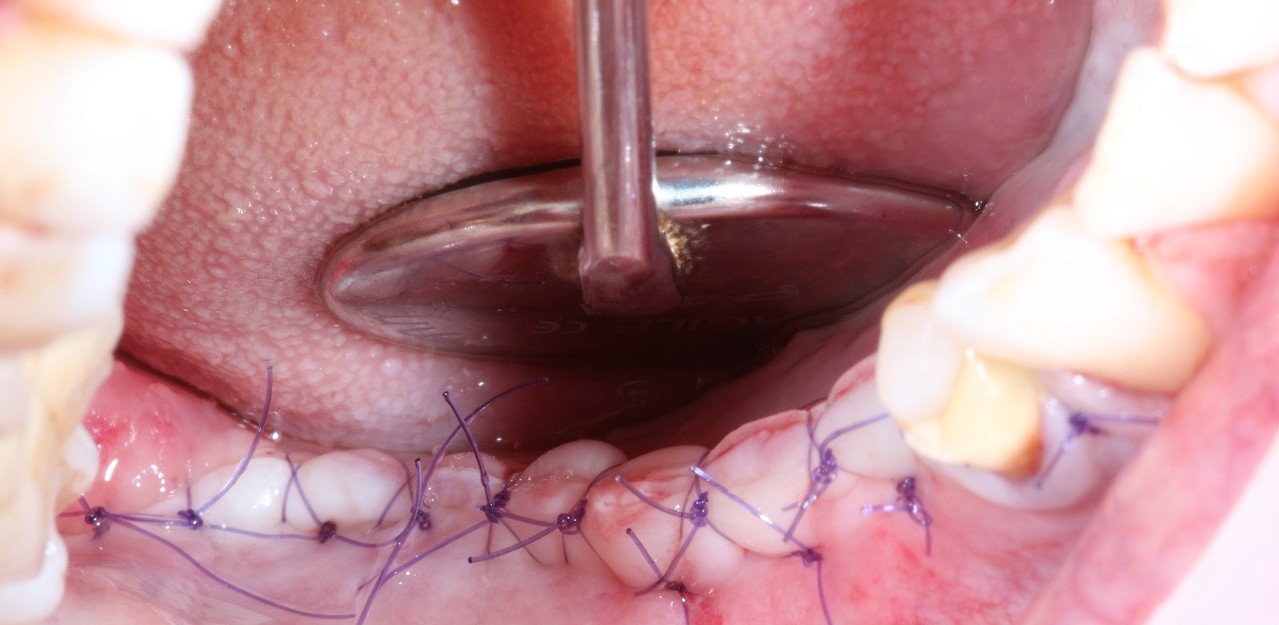

Вертикальная аугментация атрофированного альвеолярного отростка в области дистального участка нижней челюсти